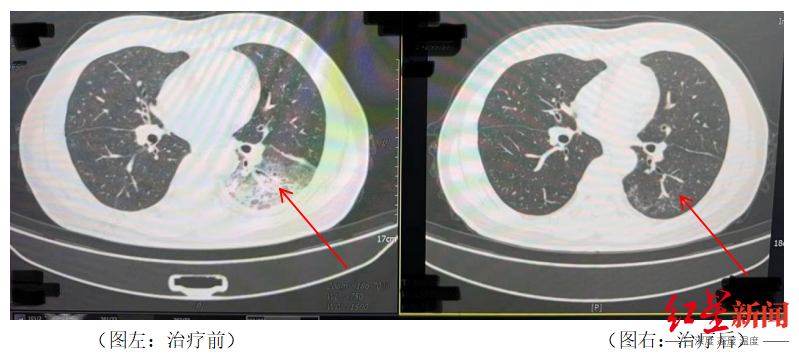

家人见状,立即将他送医。胸部CT显示李先生的左肺已出现大面积白色影像,几乎占据一半肺部。经过检测,最终确认是嗜肺军团菌肺炎。

△李先生肺部治疗前与治疗后的对比